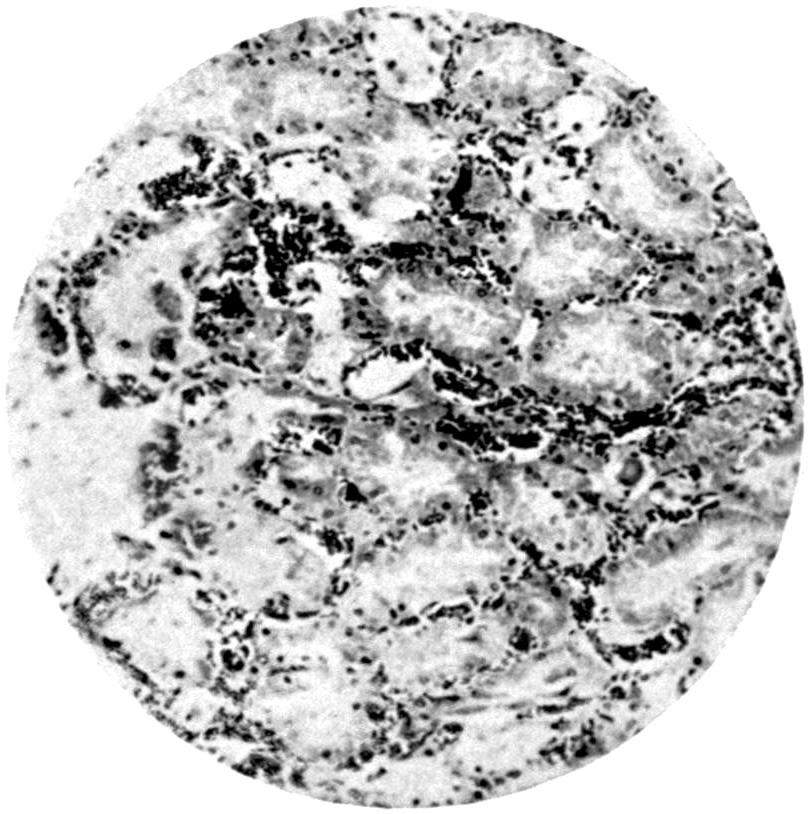

Plate IV. 276